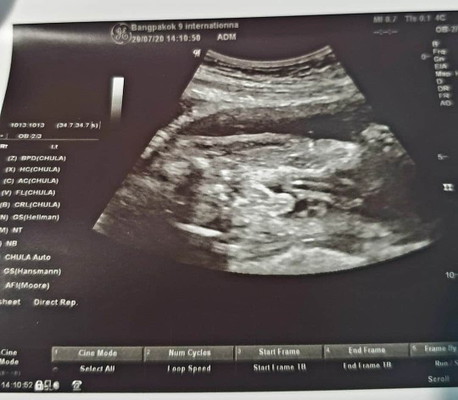

สอบถามหน่อยค่ะ ผู้หญืงหรือผู้ชายคะ ถามหมอ หมอบอกผู้ชายค่ะ แต่ให้รอดูตอนคลอดอีกที

จู๋ชัดขนาดนี้ ไม่พลาดค่ะแม่

ผู้ชายค่ะ จู๋่โผล่เเต่ไกล

ไข่ใหญ่จู๋โด่มาเลยคะ

ชัดเลยแม่ ชายค่ะ

จู๋ชัดมากแม่